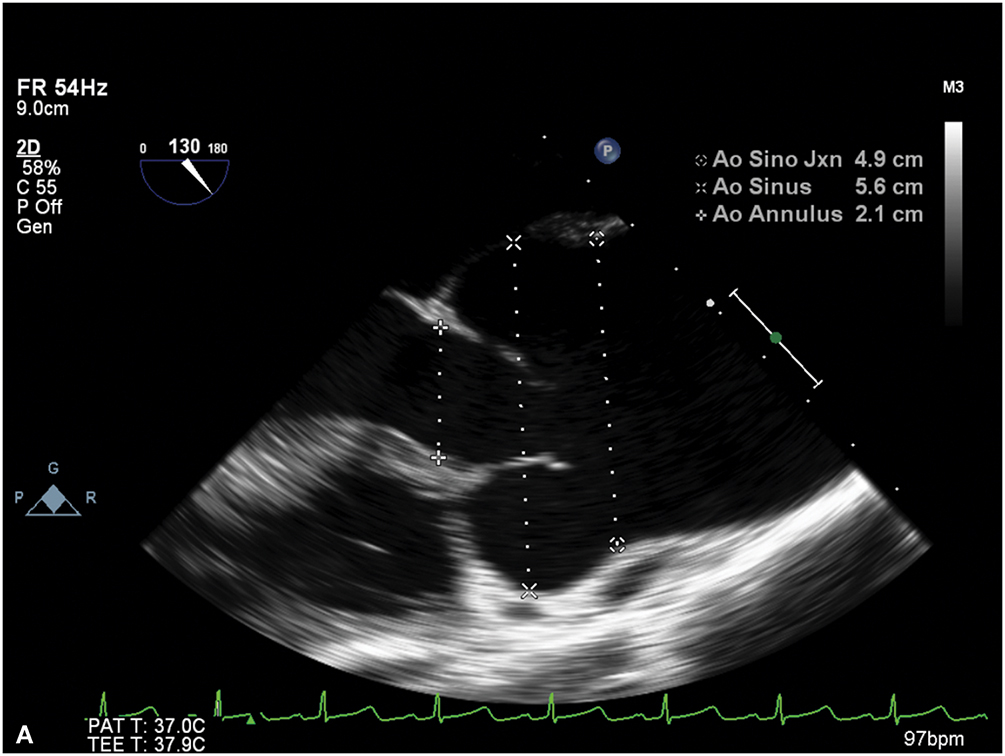

Figure 9.3.: A. Midesophageal Aortic Valve Long-Axis View on Transesophageal Echocardiography Demonstrating the Aortic Valve Annulus, Sinus, and Sinotubular Junction Dimensions at Mid-Systole.

A. Midesophageal aortic valve long-axis view on transesophageal echocardiography demonstrating the aortic valve annulus, sinus, and sinotubular junction dimensions at mid-systole. B. Ascending aorta in short axis demonstrating aneurysmal enlargement with a diameter of 5.3 cm in a young female with Turner syndrome.